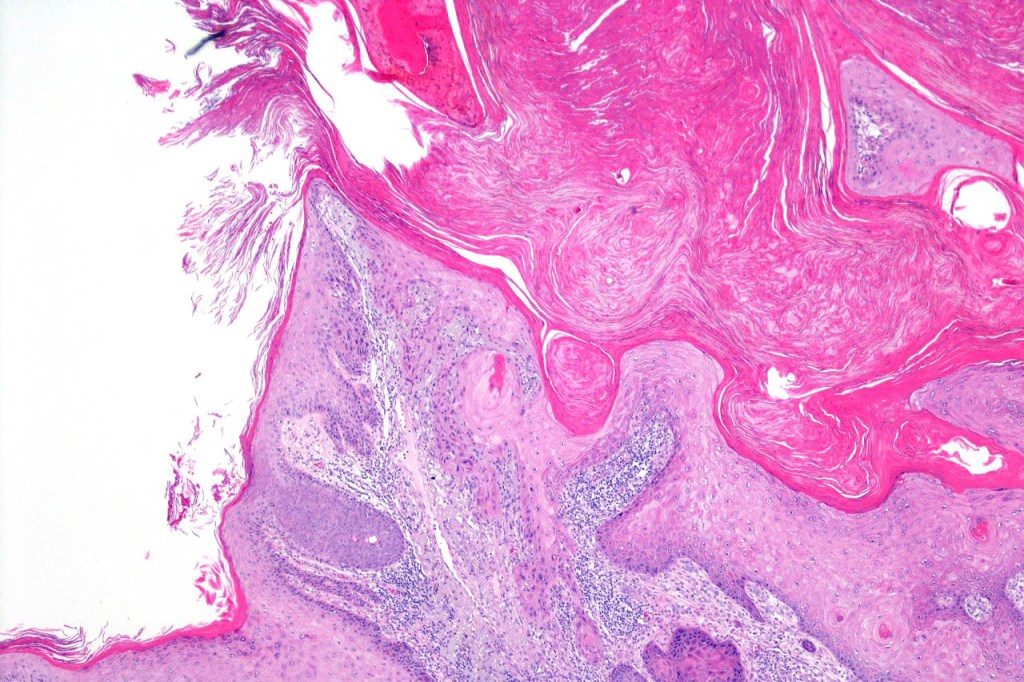

•Keratoacathoma (nowdays regarded as a variant of well differentiated squamous carcinoma) is characterized by a crateriform squamous epithelial lesion (dilated follicular infundibulum) with central keratin plug and adjacent collarette extending to the mid-dermis

•Well differentiated squamous epithelium often with a characteristic ground-glass appearance

Below is a fascinating case shared on McKee Derm by Dr. James Simpson. There is an obvious keratoacanthoma but at the edge of the lesion there is marked atypia with nuclear enlargement and pleomorphism. This is also evident in the adjacent epidermis and in the deeper nests.